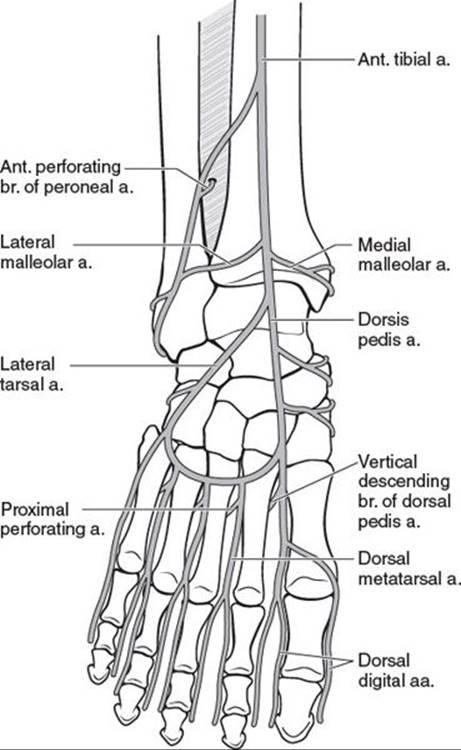

Because the foot is an end organ, many arterial–arterial anastomoses provide a duplication of inflow. These arterial–arterial anastomoses (Figure 95.2) provide a margin of safety if one of the main arteries becomes occluded. At the ankle, the anterior perforating branch of the peroneal artery is connected to the anterior tibial artery via the lateral malleolar artery. At the Lisfranc joint, the dorsalis pedis artery dives into the first interspace to connect directly with the lateral plantar artery. This vascular loop is critical in determining the direction of flow within the anterior or posterior tibial arteries, which can be antegrade or retrograde or both. In addition, the plantar and dorsal metatarsal arteries are linked to one another at the Lisfranc joint by proximal perforators and at the digital web spaces by distal perforators. Finally, the posterior tibial artery and peroneal artery are directly connected deep to the distal Achilles tendon by one to three connecting arteries. Using a Doppler ultrasound probe and selective occlusion, one can determine the patency of these connections as well as the direction of flow. This knowledge is critical in designing local flaps, pedicled flaps, and amputations.3

FIGURE 95.2. Arterial anatomy of the foot and ankle. At the ankle, the anterior tibial artery gives off the lateral malleolar artery at the level of the lateral malleolus that anastomoses with the anterior perforating branch of the peroneal artery. At the Lisfranc joint, the dorsalis pedis artery dives deep in the first interspace to join the lateral plantar artery. At the second, third, and fourth proximal interspaces, the proximal perforators link the dorsal and plantar metatarsal arteries. Not shown is the direct connection between the peroneal and posterior tibial artery deep to the distal Achilles tendon. (From Attinger C. Vascular anatomy of the foot and ankle. Oper Tech Plast Reconstr Surg. 1997;4:183, with permission.)